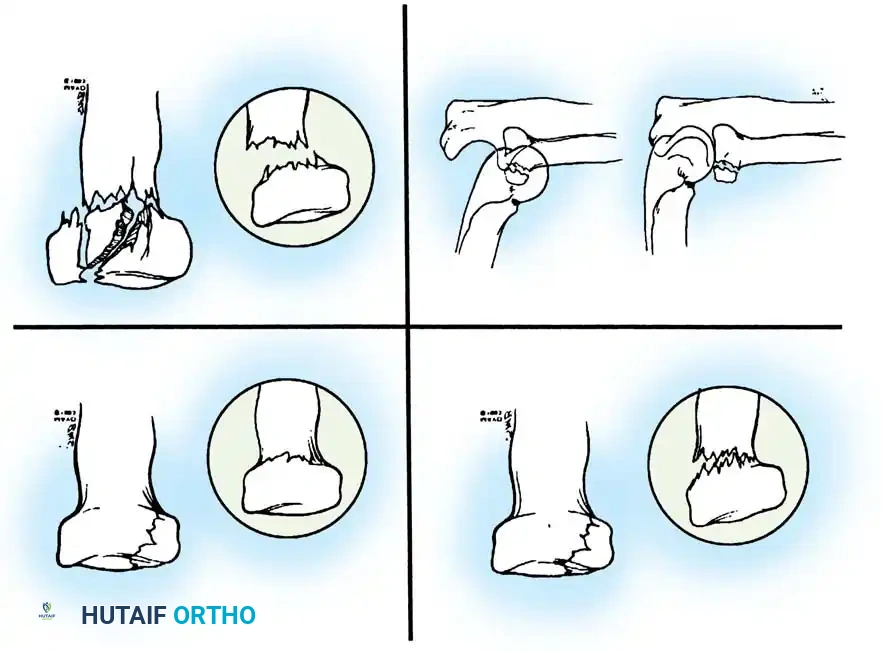

Schatzker classified olecranon fractures based on the fracture pattern and the mechanical considerations dictating the required type of internal fixation. Understanding this classification is paramount for preoperative planning.

Fig. 54-52 A-F, Schatzker classification of olecranon fractures. (From Browner BD, Jupiter JB, Levine AM, et al, eds: Skeletal trauma, Philadelphia, Saunders, 1992.)

The Schatzker classification includes:

* Transverse: Typically avulsion injuries amenable to tension band wiring.

* Transverse-Impacted: Requires elevation of the impacted articular segment and bone grafting before fixation.

* Oblique: May require lag screw fixation in addition to a neutralization plate or tension band.

* Comminuted: High-energy injuries often requiring plate osteosynthesis to prevent shortening of the greater sigmoid notch.

* Oblique-Distal: Fractures extending distal to the coronoid process, compromising elbow stability.

* Fracture-Dislocation: Complex injuries requiring rigid plate fixation to restore the stabilizing buttress of the proximal ulna.